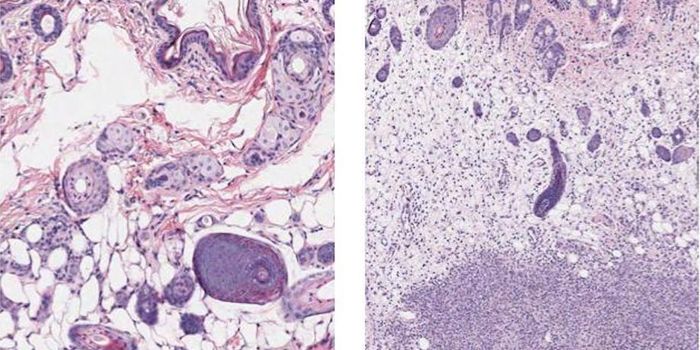

FEB 09, 2024CancerHistopathology describes the process of examining pieces of tissue using a microscope. Light microscopic (LM) exam ...